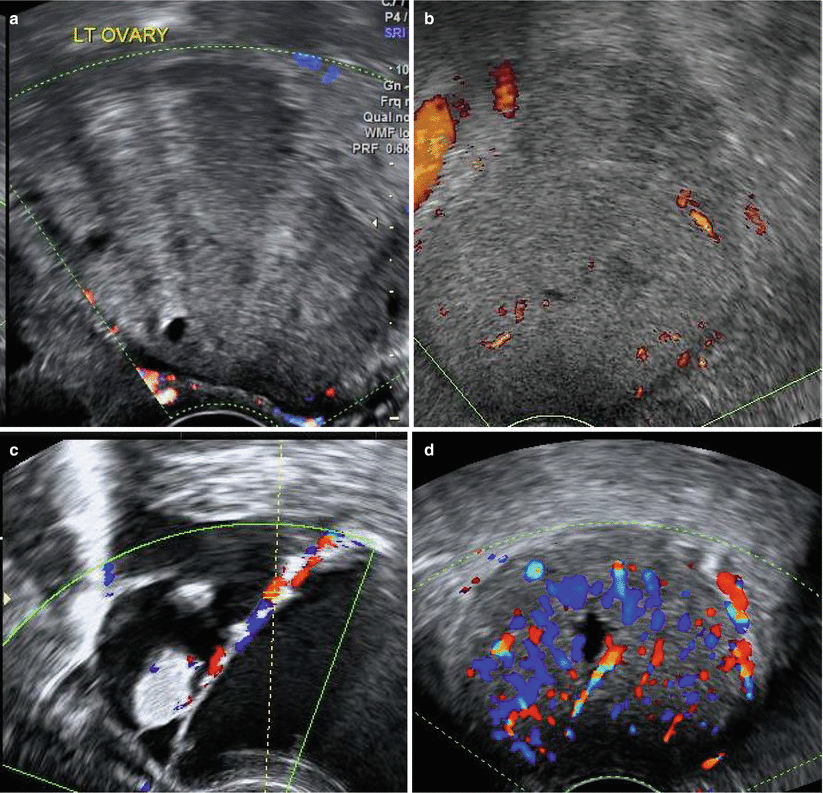

Colour index (Fig. 7.12): The most accepted method of assessing Doppler flows is colour scoring, a subjective semi-quantitative evaluation where scores are given from 1 to 4:

1 – no flow

2 – minimal flow (few colour spots)

3 – moderate flow

4 – abundant flow

The absence of flow (colour score 1) increases the likelihood of the mass being benign. Colour score of 3–4 increases the likelihood for malignancy but may also be seen in benign adnexal masses, infections, corpus luteum and trophoblastic tissue.

Fig. 7.12

Colour score: (a) Score 1 – no flow. (b) Score 2 – minimal flow. (c) Score 3 – moderate flow. (d) Score 4 – abundant flow